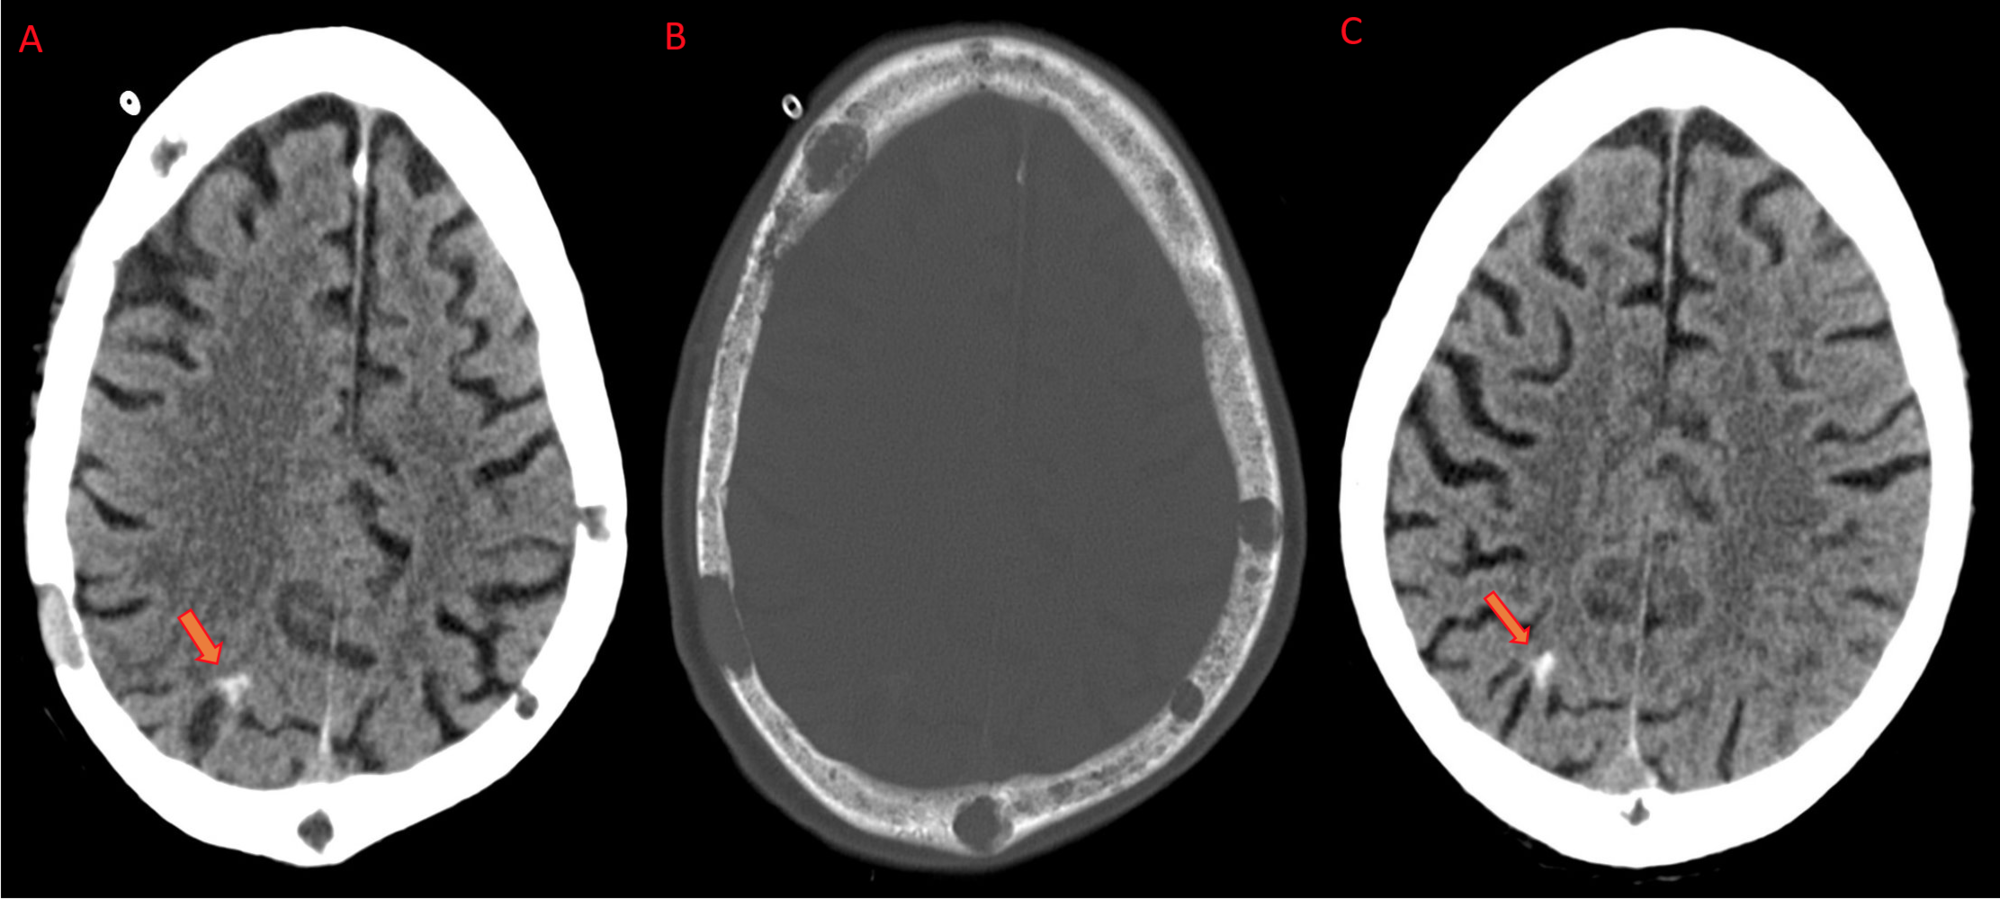

Marie deswarte, dvm, decvdi, dacvrobserving osteolytic lesions on radiographs is one of the four diagnostic criteria for multiple myeloma, so this modality plays an important role in the clinical. The recently updated durie/salmon plus staging system published in 2006 highlights the many advances that have been made in the imaging of multiple myeloma, a common malignancy of plasma cells. Osteoporosis is most common skeletal abnormality in this disease. This pattern has the most adverse prognosis. For this reason, imaging plays a major role in the management of disease in patients with mm. It once was considered in the same spectrum of plasma cell dyscrasias with polyneuropathy as poems syndrome but is now considered a separate entity. It may manifest as multiple sclerotic lesions or areas of diffuse osteosclerosis 3. International myeloma working group consensus statement and guidelines regarding the current role of imaging techniques in. Multiple myeloma imaging, that is to say using imaging studies such as mri to identify mm activity, is central to managing our mm. Osteoporosis, osteoclastic destructions, pathological fractures of the bone, spinal cord and compression can impair patients' quality of life and reduce survival. Multiple myeloma (mm), the second most common hematologic malignancy, is characterized by clonal proliferation of plasma cells. Multiple myeloma is a malignant proliferation of the plasma cells mainly affecting bone marrow, but other organs may also be involved. Dr mohammad taghi niknejad and dr ki yap et al.

The most common location is in the axial skeleton (spine, skull, pelvis and ribs) and in the diaphysis of long bones (femur and humerus). Gadolinioum (gd), according to the study linked below, encourages the growth of multiple myeloma. Gd is the agent that enhances the contrast of the many mri scans you will have during your life as a mm survivor. Marie deswarte provides the radiology perspective on this multiple myeloma case. It arises from red marrow due to the monoclonal proliferation of plasma cells and manifests in a wide range of radiographic abnormalities. In multiple myeloma, when the cancer protein level is up, the normal antibody levels are down. Multiple lytic 'punched out' lesions. Multiple myeloma (mm) is a clonal plasma cell proliferative disorder characterized by primary infiltration of bone marrow and excessive production of abnormal immunoglobulin.

Multiple myeloma is a blood cancer affecting the plasma cells of the bone marrow. Many clinical studies suggest modern imaging techniques for their greater. Multiple myeloma is characterized clinically by osseous involvement favoring the axial skeleton with associated pain and sequelae, hypercalcemia, chronic renal insufficiency, anemia, and the presence of monoclonal immunoglobulin (ig, m protein) in serum and/or urine. In multiple studies, including autopsy series 1, 9 and studies based on imaging findings , investigators have reported that the reticuloendothelial system is most commonly affected by extraosseous myeloma.one autopsy series reported splenic, hepatic, and lymph node involvement in 31%, 29%, and 23%, respectively, of patients with myeloma. Osteosclerosing (or osteosclerotic) myeloma is an uncommon form of multiple myeloma. Discussion multiple myeloma (mm) is a neoplastic proliferation of monoclonal plasma cells within the bone marrow. It is used to establish the diagnosis and to dictate the immediate need for therapy. Dr mohammad taghi niknejad and dr ki yap et al. Multiple lytic 'punched out' lesions. Multiple myeloma is a type of blood cancer arising from the uncontrolled clonal proliferation of malignant plasma cells resulting in impaired hematopoiesis, hyper production of monoclonal protein, bone tissue destruction leading and renal system alterations up to kidney failure. It once was considered in the same spectrum of plasma cell dyscrasias with polyneuropathy as poems syndrome but is now considered a separate entity. Distinctive to mm are the lucent, elliptical, subcortical shadows, especially in long. Lesions are usually multiple and found in vertebrae, ribs, skull, pelvis, and femur.

Lesions are usually multiple and found in vertebrae, ribs, skull, pelvis, and femur.